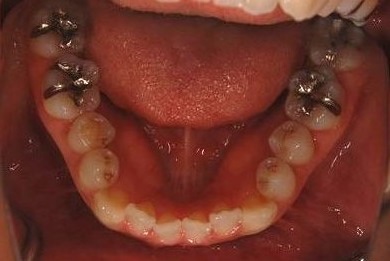

| 性別/年齢 | 女性 / 34歳 | ||||||||||||||||||||||||||||||||

| 主訴 | 以前虫歯を治療して金属を入れたところが、再び虫歯になったのか、軽くしみたり違和感がある。 | ||||||||||||||||||||||||||||||||

| 治療方針 | セラミック治療にて、審美的回復を行う。 | ||||||||||||||||||||||||||||||||

| 治療内容 | メタルボンドセラミッククラウン1本(メタルボンド用土台1本) | ||||||||||||||||||||||||||||||||

| 総治療費 | 125,685円 | ||||||||||||||||||||||||||||||||

| 治療期間 | 3ヶ月 |